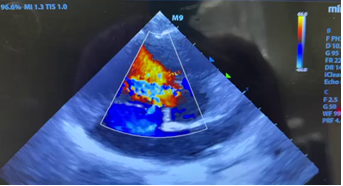

一小时后,亮亮的手术顺利完成,安全返回病房。紧接着,嘉嘉也被送进了手术室。手术十分顺利,仅历时半小时有余,嘉嘉便安全病房。术后两位患儿复查心脏彩超显示封堵器位置、形态正常,未见残余分流,均达到了预期效果。

嘉嘉术中彩超